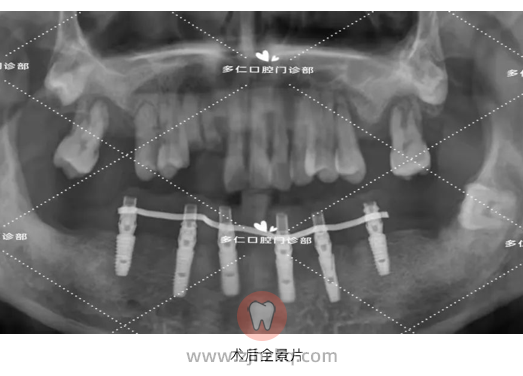

医生建议:35-31、37、42-44、48分离牙龈,拔除, 即拔即种32、34、36、42、44、46植入植体6颗,即刻修复,当天戴牙,后期恢复6-6全瓷牙冠。